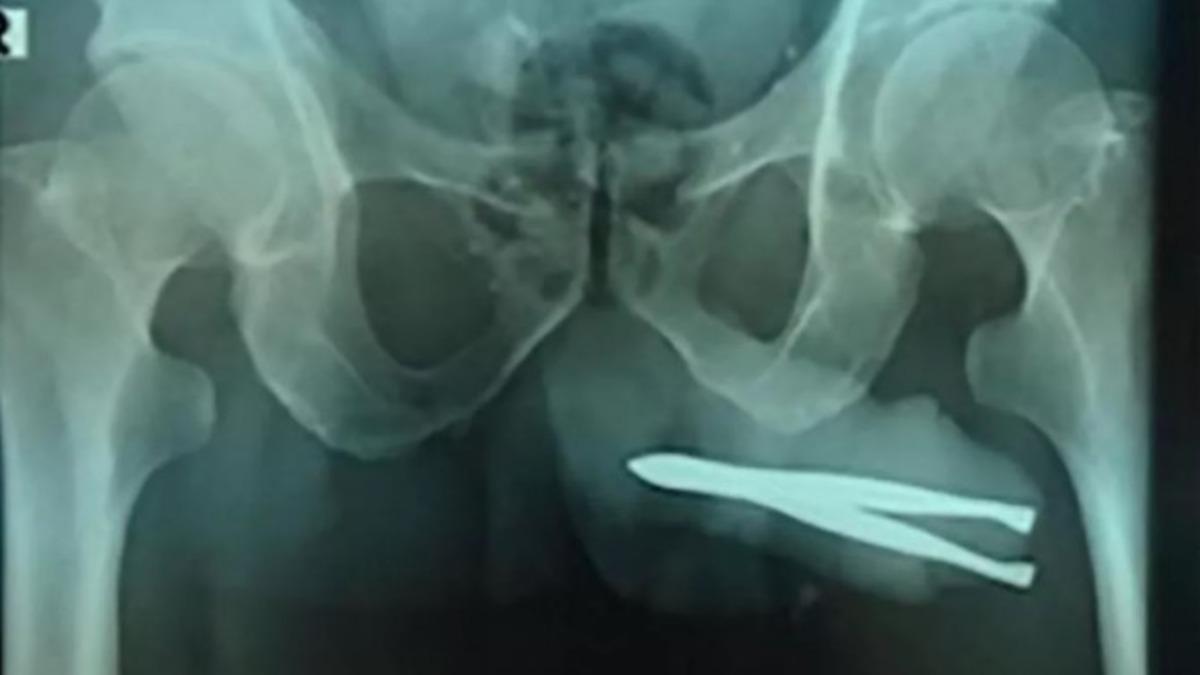

MYNET|DIŞ HABERLER Endonezya'da yaşanan bir tıbbi olay kısa sürede ilgi çekmeyi başardı. 54 yaşındaki ismi açıklanmayan bir hasta çığlık çığlığa hastaneye geldiğinde doktorlar röntgen çekerek nedenini öğrenmek istedi.

İsmi açıklanmayan 54 yaşındaki adam, acıya rağmen mucizevi bir şekilde idrarını yapmayı başardı. Hasta her tuvalete gittiğinde acı içinde çığlık atıyordu. Onu tedavi etmek için, anestezi altında cımbızın cinsel organından çıkartılması gerekiyordu. Cerrahi operasyonla nesne çıkartırıldı.

Nadir görülen bir olayın vaka çalışması, "Üretra yaralanmaları asla yaşamı tehdit edici değildir, ancak tedavi edilmezse önemli morbiditeye yol açabilir. Yabancı bir nesne sokmak, kendine zarar verme için yaygın bir uygulamadı" ifadeleriyle açıklandı.